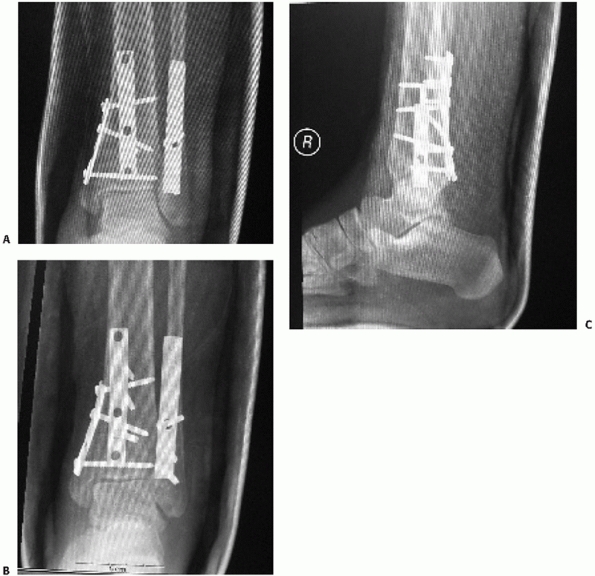

adequate reduction with the foot in neutral have been established and

validated.95,177

Parameters that suggest unstable fracture patterns include lateral

malleolar displacement greater than 2 mm with resultant talar shift on

the AP or lateral, significant medial malleolar displacement, deltoid

ligament disruption defined by greater than 5 mm medial clear space,

syndesmosis injury identified by tibial-fibular clear space greater

than 5 mm or tibial-fibular overlap of less than 10 mm (both on the

AP), or a tibial-fibular overlap of less than 1 mm on the mortise view (Fig. 57-3).

the talocrural angle and the “ball sign.” The talocrural angle is

measured between a line perpendicular to the tibial plafond and a line

connecting the tips of the medial and lateral malleoli. Normal range is

83 ± 4 degrees or a deviation from the talocrural angle measurement on

the contralateral side197 (see Fig. 57-3).